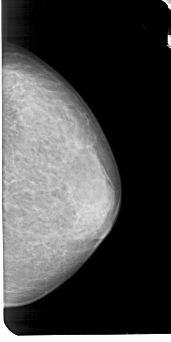

A_1947_1.RIGHT_CC

RIGHT_CC LINES 5116 PIXELS_PER_LINE 2551 BITS_PER_PIXEL 12 RESOLUTION 43.5 NON_OVERLAY